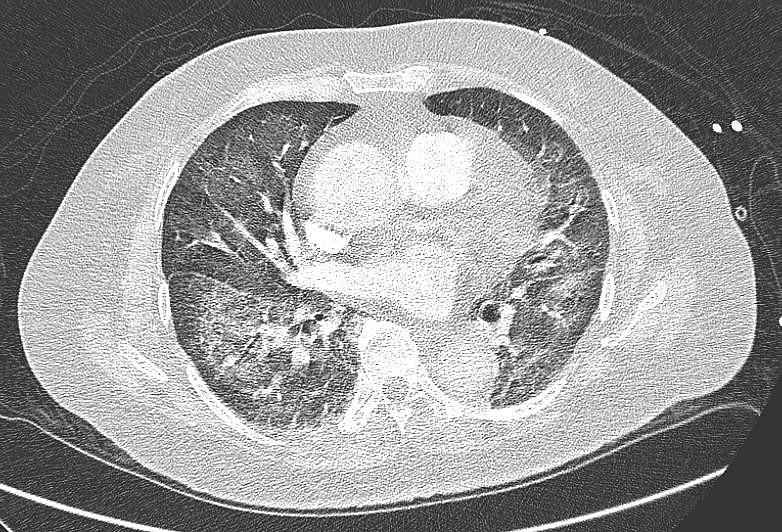

图2. 胸部CT显示双肺网状改变明显改善

出院时,患者每天24小时使用3升氢/氧治疗。她的日常生活活动依赖他人,行走需要辅助。两周后在门诊复查时,她未携带氧气,能够独立行走,无任何困难。此时,她的临床症状已完全缓解。肺部检查也显示双侧无湿啰音。胸片显示肺野网状阴影已消失。1个月后进行的胸部CT显示双肺网状改变显著改善(图2)。她对氢/氧治疗耐受良好,无不良事件。她最终也在4周内逐渐停用泼尼松龙。随后决定不再继续化疗,并开始对右侧乳腺进行放疗。自化疗停止以来,她的疾病仍处于缓解期,并且在2年的随访中临床状况良好。